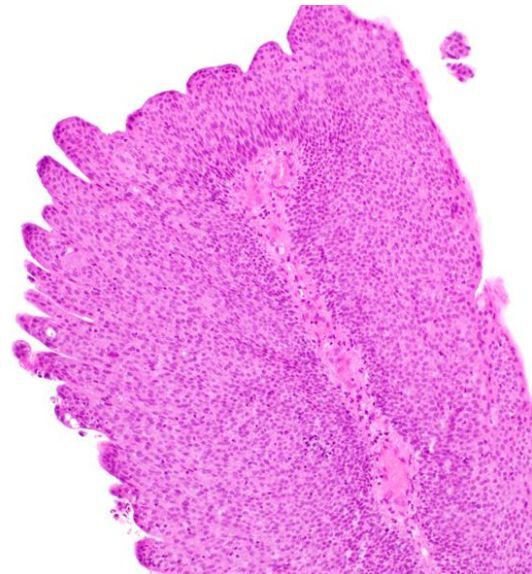

Urothelial papilloma

Note that while it is definitely papillary, the normal epithelial thickness is preserved.

10% will recur, but only 1% will progress to a carcinoma.

Treated with TURBT